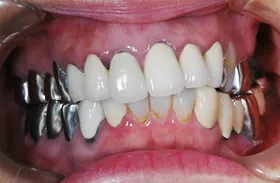

■治療前:上下顎 義歯での食事に満足されていない

■治療後:上下顎 複数本のインプラントを使い固定式で治療

| 主訴 | 現在義歯を使用しているが、しっかりと咬んでなんでもおいしく食事したい |

| 治療方法 | 上下顎 複数本のインプラントを使用しての治療 |

| 治療期間 | 約1年 |

| 通院回数等 | 約20回 |

| 費用 | 約600万円(税込) |

| リスク・副作用 | 術後の腫れ・痛み |